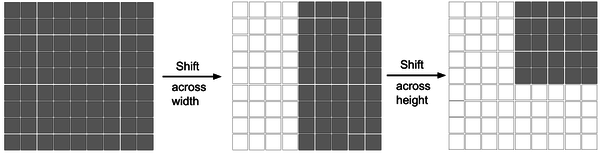

3.1.2 Shifted MLP

During the shifted MLP stage, before tokenization, the first operation performed is to shift the axes of the convolutional feature channels, aiding the multilayer perceptrons in focusing solely on the positional features of the convolutional features. To introduce more locality into the originally entirely global model, a window-based attention mechanism is employed at this stage, enabling the model to better integrate both global and local feature information. As illustrated in Figure 5, the shifted MLP schematic depicts features moving across width and height within two blocks, dividing features into different partitions and shifting their positions along the specified axes.

|

| Figure 5. Diagram of the shifted MLP (multilayer perceptron) |